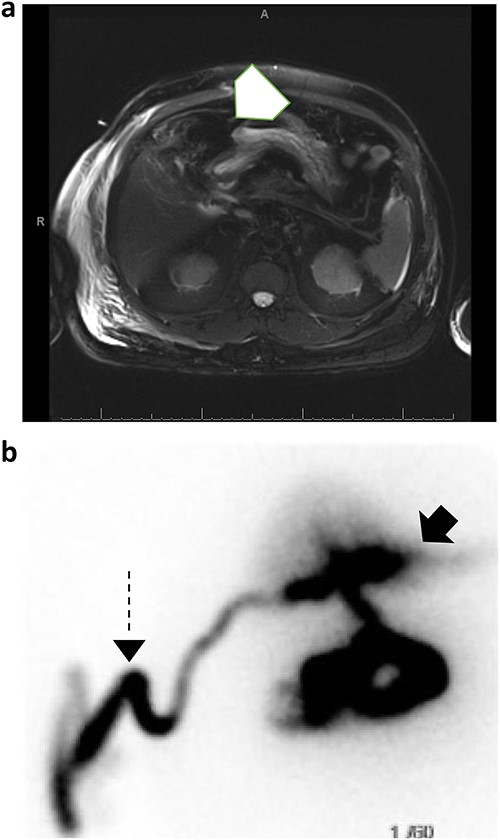

The patient was started on cefepime and metronidazole, and a Jackson Pratt (JP) drain was placed in the right upper quadrant by interventional radiology. The JP drain output was milky and blood-tinged with daily outputs ranging from 200 to 1500 mL. JP drain fluid triglyceride levels were > 525 mg/dL. Lymphatic injury was suspected at this time and the patient was started on a low-fat, high protein diet and octreotide. A MRCP was performed to evaluate for a possible concurrent unrecognized pancreatic injury, which showed evidence of abdominal free fluid (Fig. 2a). A subsequent hepatobiliary iminodiacetic acid (HIDA) scan revealed a bile leak that was adequately controlled by the drain (Fig. 2b). A first attempt at endoscopic retrograde cholangiopancreatography (ERCP) was unsuccessful due to ampullary stenosis. Therefore, the patient underwent advanced ERCP with endoscopic ultrasound which revealed a normal biliary tree with no obvious bile leak, at which time a common bile duct sphincterotomy with placement of a 10 French 7 cm plastic stent.

(a) MRCP with and without IV contrast identifies trace free fluid in gallbladder fossa (white arrow); (b) subsequent HIDA scan confirms right hepatic subcapsular bile leak (black arrow) adequately drained by percutaneous catheter (dashed arrow).